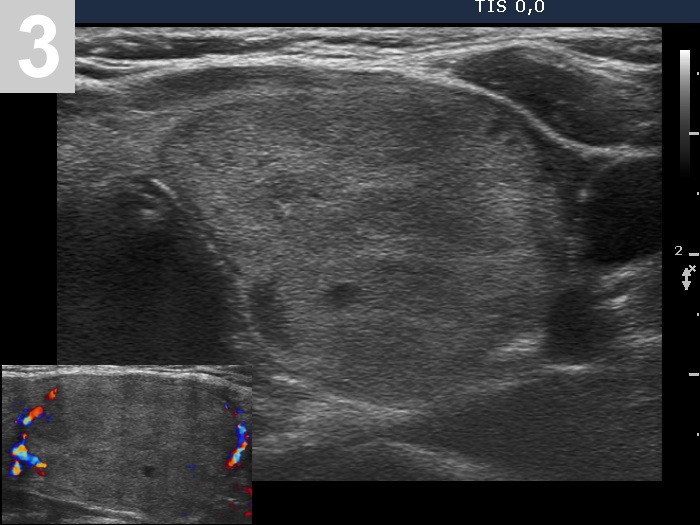

3 US of thyroid cancer

Pre- and postoperative ultrasound in thyroid cancers

Cases to be discussed on January 18, 2024